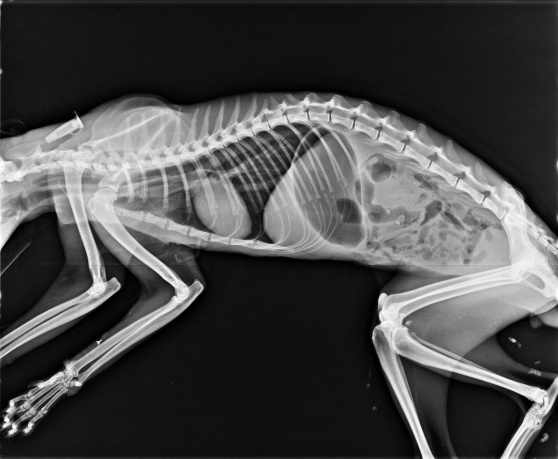

其中有一隻鼻器管炎和腹瀉嚴重的貓咪,多日不吃不喝,灌食困難,腹瀉癱軟在沙盆中,上收容所數量暴增,擔心疾病傳染擴散且再拖下去會延誤病情,緊急送往醫院治療,管管因鼻膿無法聞到食物的味道,兒不願意進食,進食量不夠有脫水的狀況,放置鼻餵管灌食並給與輸液治療,早晚噴霧給與止瀉藥和抗生素,控制腹瀉和鼻膿的狀況,隔天管管明顯舒服很多,雖然還是累累的,但已經會用矇矓小眼深情望著醫師,治療的時候還偷蹭醫師的手手,慢慢越來越撒嬌也大口大口吃著食物,但還是會打噴嚏鼻塞,經過19天的治療管管雖然還有一點鼻水腹瀉,但已經可以居家照顧,已帶回安養之家,目前已經是頭好壯壯,醫療費用還請各位幫忙。